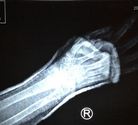

诚念“法轮大法好” 八旬老人骨折16天愈合(图) 【明慧网】

(2019-2-24发表)